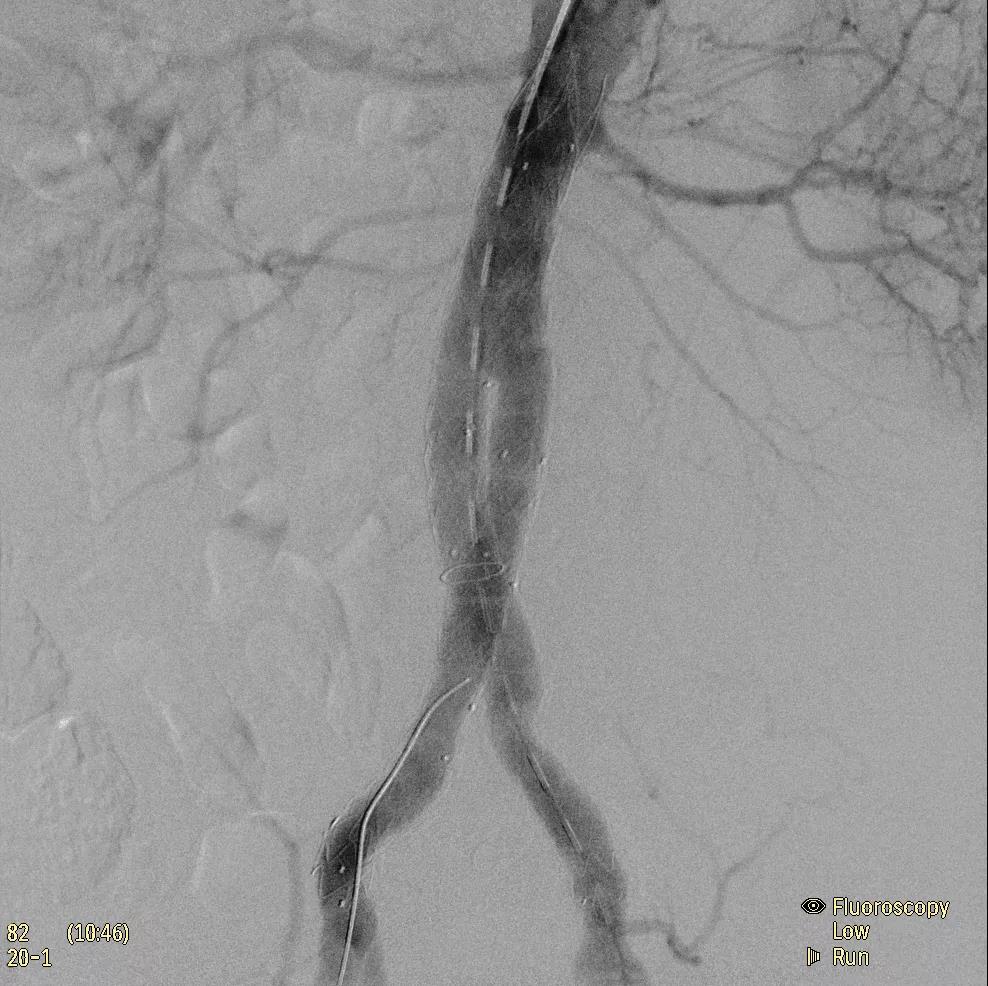

飛利浦于2019年2月18日宣布推出帶扁平探測器的移動式C臂Zenition 70。Zenition 70使用飛利浦第四代Flat Detector系統(tǒng),具有卓越的成像清晰度和靈活性,可執(zhí)行各種情況。

據(jù)器械之家了解到,移動式C型臂是X射線系統(tǒng),可帶入手術(shù)室(OR),在整形外科、創(chuàng)傷和血管手術(shù)等各種手術(shù)過程中提供實時圖像引導(dǎo)。Zenition70使醫(yī)院能夠最大限度地提高OR性能,增強臨床能力并為員工提供高質(zhì)量的用戶體驗。

( Zenition 70匯集了圖像捕獲,圖像處理,易用性和多功能性方面的創(chuàng)新。)

在快速增長的圖像引導(dǎo)微創(chuàng)手術(shù)領(lǐng)域 ,手術(shù)干預(yù)的范圍和復(fù)雜性在繼續(xù)增加,需要治療的患者數(shù)量也在增加。為了以更低的成本治療更多的患者,醫(yī)院需要具有不同能力的多功能C臂組,以便容易地適應(yīng)不同類型的手術(shù)和不同操作者的需要。Zenition 70易于在手術(shù)室之間移動,易于在患者周圍定位并且操作直觀。

飛利浦Zenition 70支持整個醫(yī)療保健機構(gòu)提高OR性能。平臺類似平板電腦的用戶界面和簡單的統(tǒng)一工作流程意味著一旦操作員學(xué)會在平臺上使用一個系統(tǒng),他們就可以輕松地操作它們。該系統(tǒng)可在任何介入或外科手術(shù)過程中快速直觀地拍攝傻瓜相機。Zenition的緊湊設(shè)計,位置記憶功能(僅適用于Zenition 70)和BodySmart軟件,即使在圖像增強器或平板探測器的邊緣也能捕捉快速一致的圖像,將C臂重新定位的需求減少45%。

( Zenition 70采用與Azurion平臺相同的圖像處理算法。

為了獲得清晰的高質(zhì)量圖像,Zenition 70 采用了與公司Azurion平臺相同的圖像處理算法,可提供患者解剖結(jié)構(gòu)的高清可視化和更大的可視區(qū)域。飛利浦的MetalSmart軟件等功能可確保圖像質(zhì)量,該軟件可自動調(diào)整圖像的對比度和亮度,以便在視野中存在金屬物體(如植入物)時提高圖像質(zhì)量 - 這一特性使Zenition 70在整形外科中特別有用。